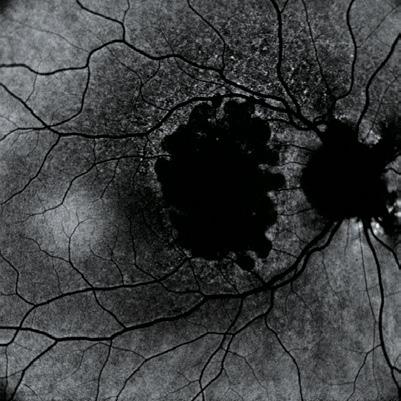

Post-paediatric cataract surgery Glaucoma: A: 3.5 years old child with cataract surgery done in infancy. Glaucoma with enlarged corneal diameter and a dislocated IOL are seen. One previous Ahmed glaucoma valve (AGV) in supero-temporal quadrant has failed to control IOP adequately; B: A second AGV plate is sutured in the infero-temporal quadrant. A closed chamber vertical translocation of haptics to glued IOL is then done sitting temporally, taking advantage of smaller vertical diameter of cornea; C: Adequate length of the externalised haptics of the IOL is seen; D: Haptics are tucked in. A well-centred IOL is seen. The AGV tube tip is positioned posterior to the iris in front of the IOL. Adequate vitrectomy is performed during IOL translocation as well as after inserting the tube tip